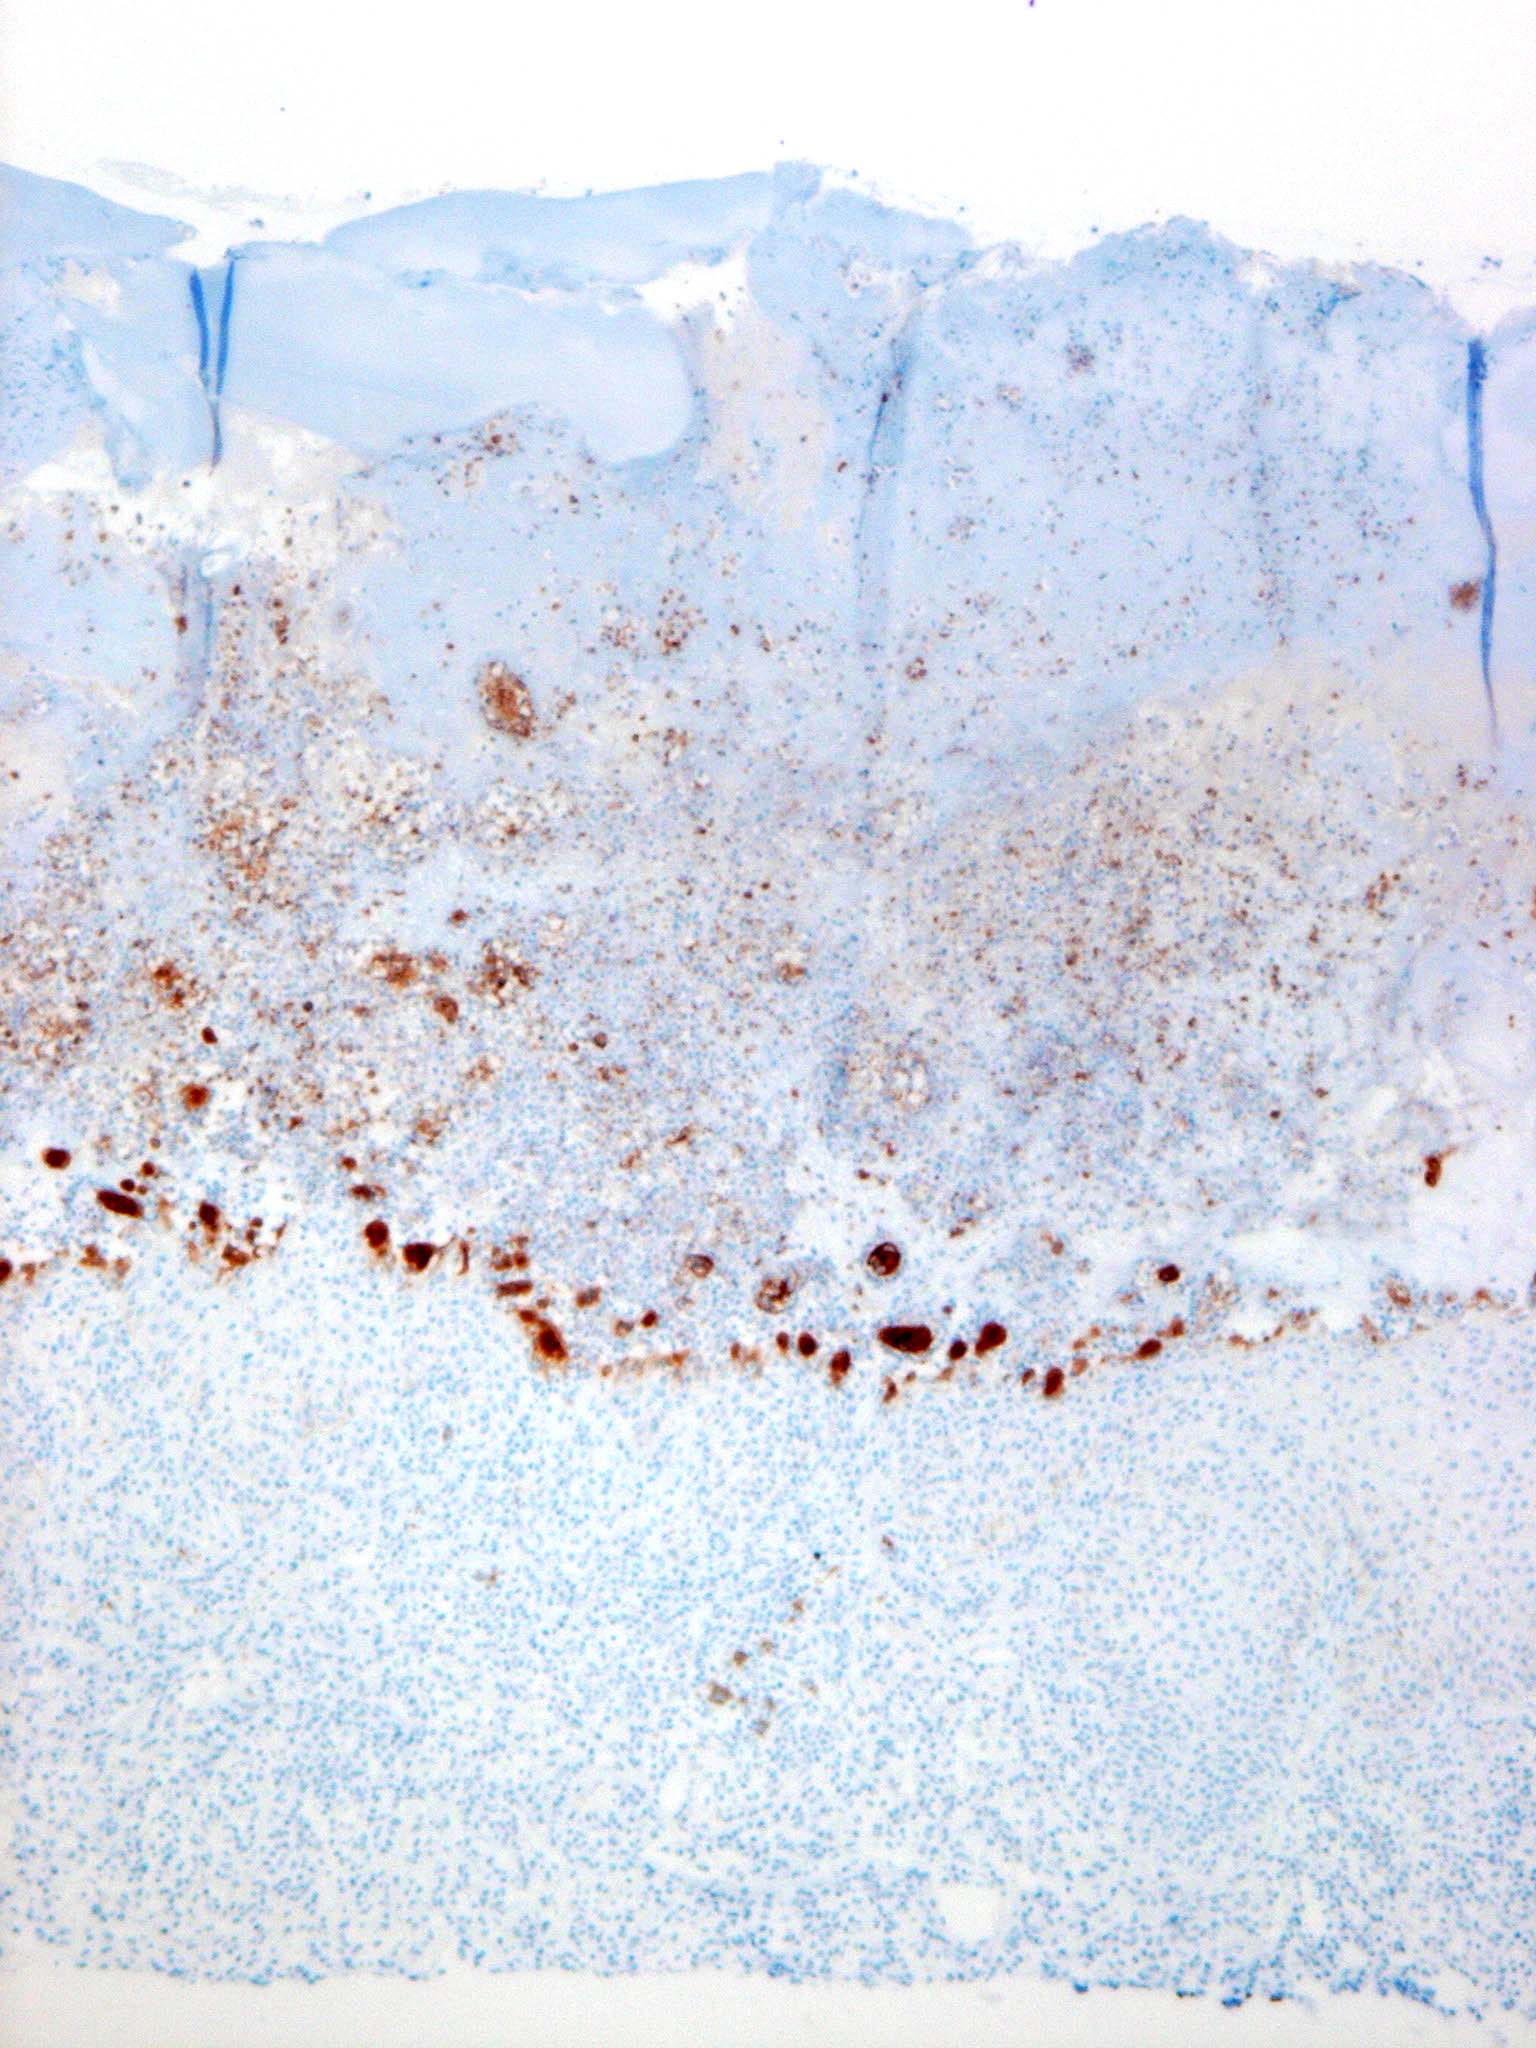

Herpes simplex = العقبول البسيط